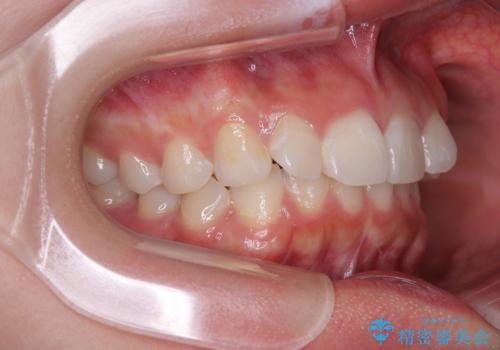

- 前歯のデコボコと突出感を気にして来院された患者様です。

極力目立たない装置を希望とのことで、インビザラインを用いて非抜歯で矯正治療を行うこととしました。

事前に親知らず2本を抜歯し、多少歯列を後方に移動できるように準備をした上で、なるべく歯と歯の間を削ることなくデコボコを解消できるように計画しました。